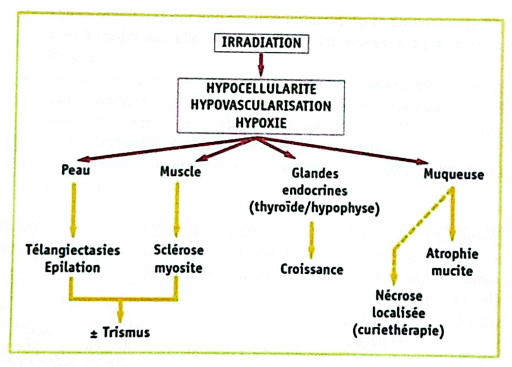

Théorie des « 3 H » de Marx

- Hypocellularité, Hypoxémie, Hypovascularisation :

- Bases de la physiopathologie, fondées sur des séries cliniques et preuves histologiques.

- Réduction des capacités métaboliques, de cicatrisation et de réparation.

- Hypovascularisation démontrée par des mesures de teneur en oxygène (tissus irradiés vs sains).

- Fondement du traitement par oxygénothérapie hyperbare.